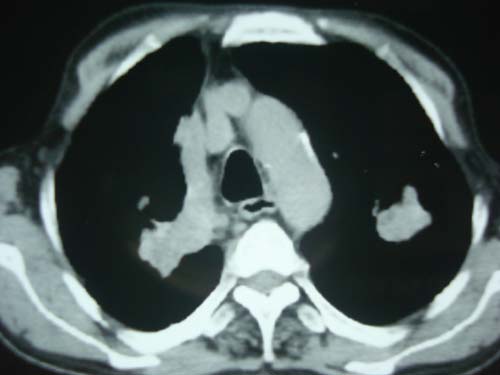

男性,45岁,胸疼,低热,抗炎治疗后症状缓解拍片检查发现左上肺有高密度灶,考虑结核,做ct示条件有限采集了部分图像,图像质量差请谅解

病灶有分叶 毛刺 左侧叶裂上移 考虑肺癌可能性大 建议穿刺

右上肺结核,左上肺周围型肺癌可能性大

考虑两肺上叶继发性肺结核;肺气肿(多发肺大泡)。